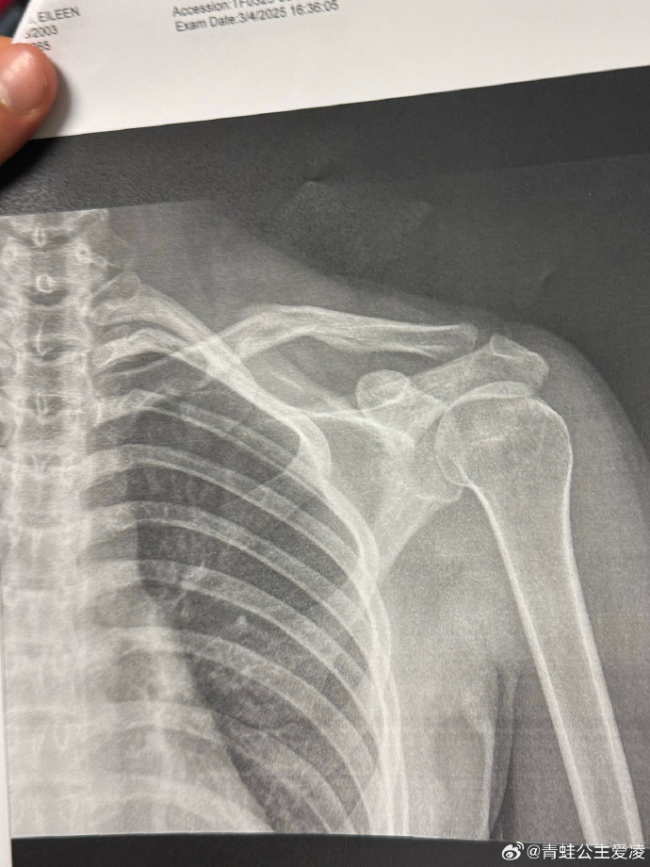

2025年3月9日,谷爱凌在酬酢媒体上晒出肩部骨折的X光像片。8月16日,她再次因“东说念主为事故”受伤,并号召寰球不要在她磨砺时找她摄像合影。9月11日,她在酬酢平台晒出康复理疗的像片,示意已规复上雪,每天进行长达10小时的康复和理疗。